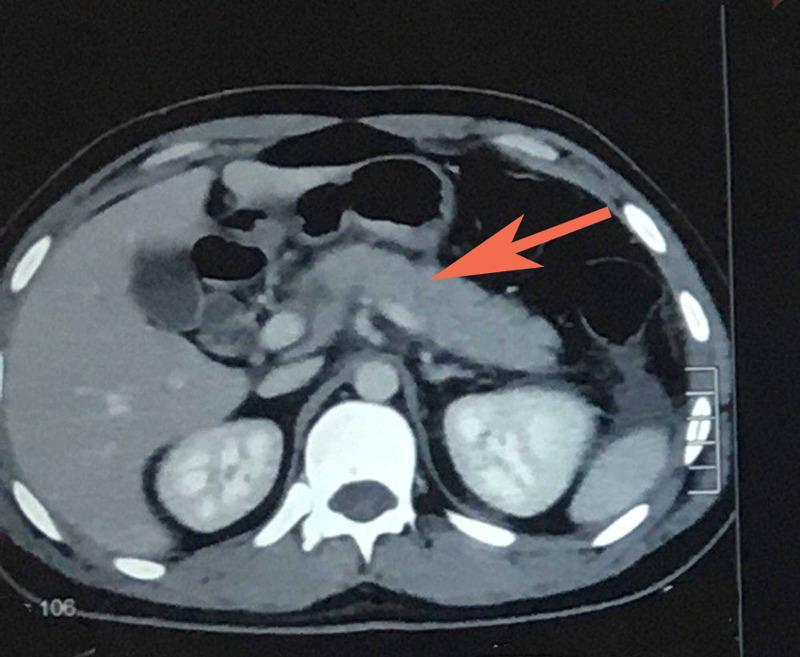

Ascariasis is the most common helminthic infection. It is most common in children of tropical and developing countries where the transmission is by contamination of soil by human feces or use of untreated feces as fertilizer. Transmission in most endemic areas is via person to person contact. We hereby present a case report of acute pancreatitis due to ascariasis. Twenty-five-year-old male patient presented to us with chief complaint of acute epigastric pain radiating to back and associated with vomiting. Initial lab investigations revealed increased serum amylase and lipase. Probable diagnosis of acute pancreatitis was made. CT scan was done and report revealed bulky pancreas, and significant peri-pancreatic fat stranding. He was managed symptomatically with intravenous fluids, analgesics, anti-emetics and enteral nutrition. However, the cause remained undetermined as we ruled out the possible etiologies of acute pancreatitis until one day the patient vomited a 15-cm round worm. Thereafter, his condition improved dramatically. This is one of the first few case reports of ascariasis-induced pancreatitis from Pakistan and the first one from Baluchistan province of Pakistan. Thus it highlights ascariasis as possible etiology of acute pancreatitis in regions where ascariasis is geographically endemic.

蛔虫病是最常见的蠕虫感染。在热带地区和发展中国家的儿童中最为常见,其传播途径是人类粪便污染土壤或使用未经处理的粪便作为肥料。在大多数流行地区,传播是通过人与人之间的接触。我们在此报告一例由蛔虫病引起的急性胰腺炎病例。一名25岁男性患者因急性上腹部疼痛放射至背部并伴有呕吐前来就诊。初步实验室检查显示血清淀粉酶和脂肪酶升高。做出了急性胰腺炎的可能诊断。进行了CT扫描,报告显示胰腺肿大,胰腺周围有明显的脂肪组织浸润。对他进行了对症治疗,包括静脉输液、止痛、止吐和肠内营养。然而,病因仍未确定,因为我们排除了急性胰腺炎的可能病因,直到有一天患者吐出一条15厘米长的蛔虫。此后,他的病情显著改善。这是来自巴基斯坦的关于蛔虫病诱发胰腺炎的少数病例报告之一,也是来自巴基斯坦俾路支省的首例报告。因此,它突出了在蛔虫病地方性流行的地区,蛔虫病可能是急性胰腺炎的病因。